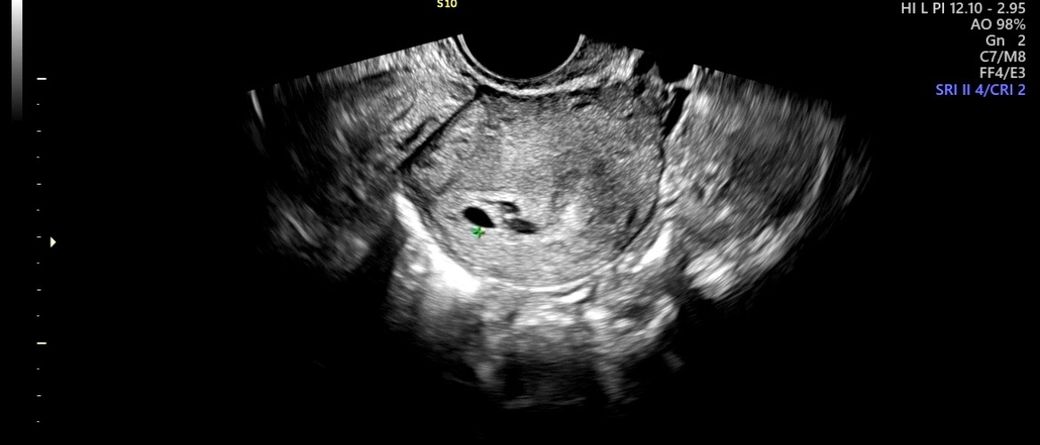

아기집 옆쪽으로있는건 뭘까요 ? 알려주세요

왼쪽이 아기집이라고 하셨는데 (0.54cm)

옆쪽에 두개 동그란건 뭘까요??

피고임인가요 ?? ㅠㅠ 유산기있을까 걱정됩니다